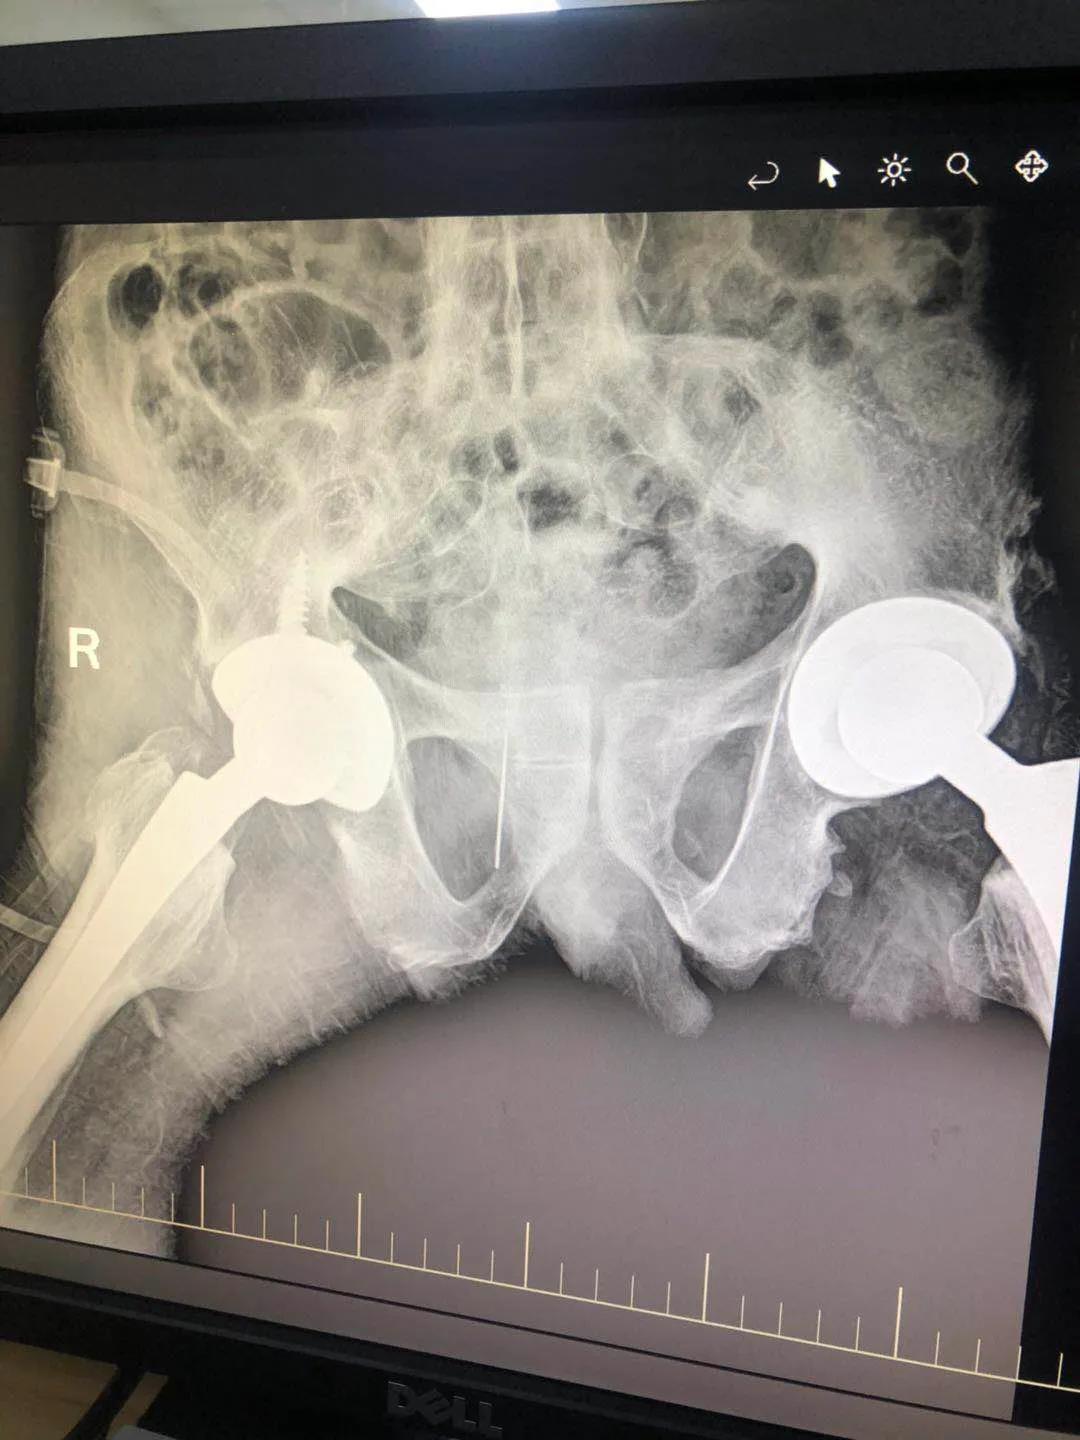

髖關(guān)節(jié)置換治療

髖關(guān)節(jié)疾病終末期股骨頭塌陷或關(guān)節(jié)破壞較重,只能采用髖關(guān)節(jié)置換、治療,骨二科采用微創(chuàng)Super-path入路和DAA入路進(jìn)行髖關(guān)節(jié)置換,患者術(shù)后當(dāng)天即可下床活動,術(shù)后無痛管理,加速患者術(shù)后康復(fù)及早日重返社會。

全髖關(guān)節(jié)置換